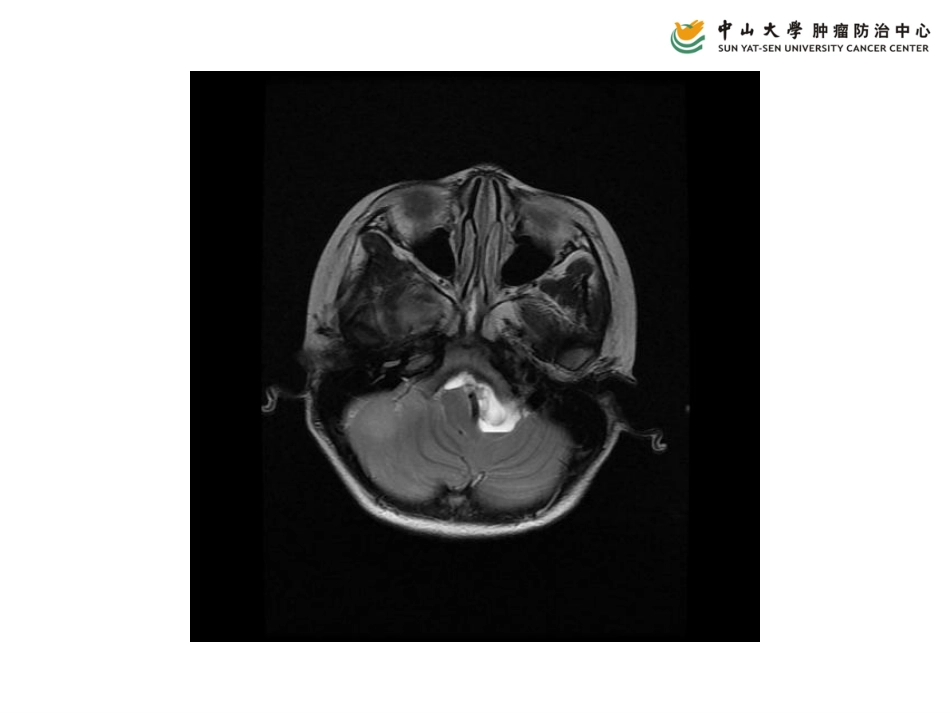

病例二•男,7岁•头痛2月余,间中呕吐1月余•患儿2月前无明显诱因出现头痛,阵发性,程度一般,能忍受。无恶心呕吐,无抽搐。1月前出现呕吐,为胃内容物,呈喷射性•足月顺产,出生时无窒息抢救史,生长发育正常